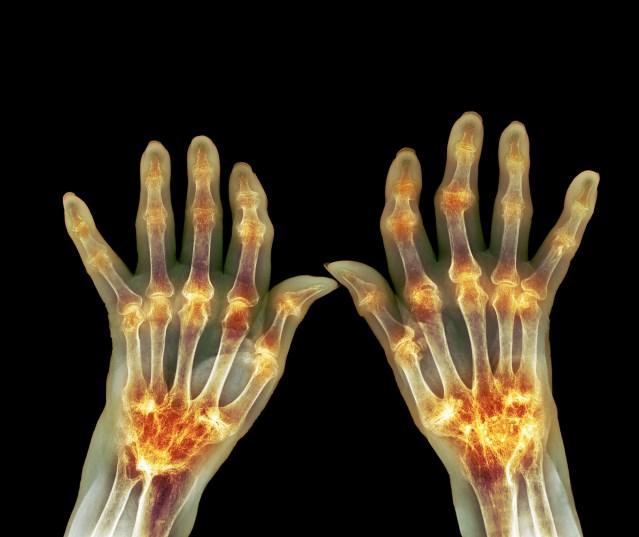

It’s early morning. A cold, damp feel is in the air. You’re dressed for the elements, but a day of work awaits, maybe you’re operating the Skidder, or loading the logging truck, or are fortunate to be in the heated cab of the Forwarder. You already notice the stiffness in your hands, the bit of redness and swelling. You have difficulty making a fist.

These are most likely symptoms of arthritis. The CDC says that about one in four adults and fully half of all people over 65 suffer from arthritis. According to the logging industry of Maine, the average age for loggers is 50.

Like machinery, our joints need lubrication and cushioning. We often begin to lose this as we age, and working our own unprotected joints can be just as problematic as operating ungreased machinery. Arthritis causes pain, inflammation, and limited range of motion. Osteoarthritis is the most common form typically affecting hands, hips, knees, feet and lower back and is the most treatable.